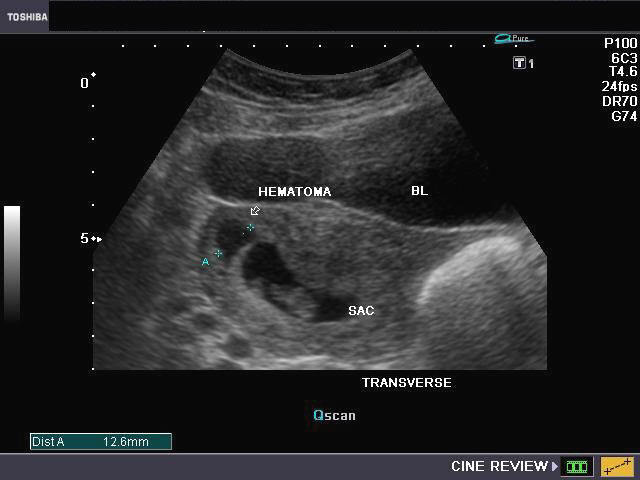

Синяков узи

Синяков узи 111 фото